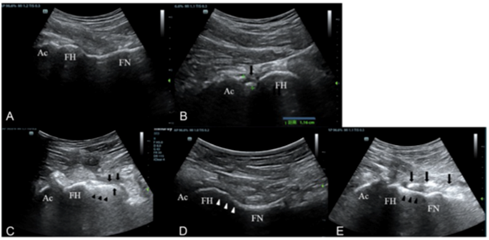

为了探索超声诊断髋臼前上盂唇损伤的效果,我科以关节镜手术作为诊断的金标准,对比了超声与磁共振成像(MRI)在髋臼前上盂唇损伤诊断中的效能。研究共纳入了195名患者,通过详尽的数据分析,我们发现在诊断髋臼前上盂唇损伤时,超声的灵敏度为68.5%,特异度为81.8%,阳性预测值为98.4%,阴性预测值为13.4%,准确度为69.2%。MRI的灵敏度为84.8%,特异度为63.6%,阳性预测值为97.5%,阴性预测值为20.0%,准确度为83.6%。尽管超声在灵敏度方面略逊于MRI,但其特异度和阳性预测值却更胜一筹。值得一提的是,超声还具有诸多优势,如价格低廉、检查过程相对快速、无创、可动态评价等。这些特点使得超声在临床实践中具有广泛的应用前景,成为评价髋臼前上盂唇损伤的可行方法。这一研究成果已得到欧洲医学和生物学超声学会联合会(EFSUMB)的认可,并被纳入其临床应用指南。

此外,我科进一步进行深入研究,评估超声检查作为MRI替代方法在临床评估髋关节囊厚度的可行性,研究发现通过超声和MRI获得的关节囊厚度测量结果显示出良好的一致性,表明超声可以在临床实践中替代MRI来测量髋关节囊厚度。同时,检验了定性和定量超声标准在诊断前上髋臼盂唇撕裂中的诊断性能,研究发现盂唇异质性回声是诊断前上髋臼盂唇撕裂的敏感标准,盂唇旁囊肿、盂唇局部高回声区和股骨头颈皮下囊肿是特异性标准。通过超声测量的前上髋臼盂唇的横截面积可以作为定量标准来诊断髋臼盂唇撕裂,结合盂唇的定性标准可以提高诊断前上髋臼盂唇撕裂的灵敏度和准确度。